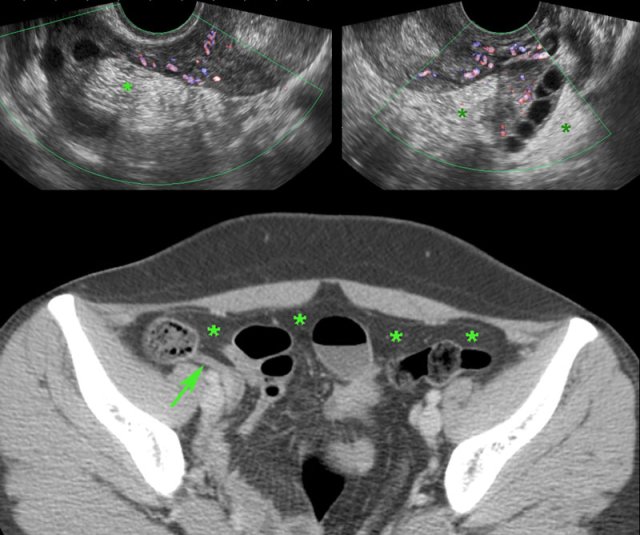

TOA case 2

Young

woman presenting with severe acute abdominal pain clinically suspect for perforated

appendicitis.

Lab-findings at admission: WBC 10.6 - CRP 6 Two days later: WBC 19.7 - CRP 459

US showed a large inhomogeneous masses left and

right of the uterus, suspect for tubo-ovarian abscess (TOA).

There

was also a paralytic ileus with secondary wall thickening of small bowel (b.) and

hyperechoic preperitoneal and mesenterial fat.

Puncture of a little ascites yielded

2 cc of yellow, turbid fluid.

CT

confirmed the US findings but additionally demonstrated a pyosalpinx (p.)

within the tubo-ovarian mass on the right side. Antibiotics are started intravenously.

Two

days later PCR of both cervical and urethral probes as well as the punctured

fluid were positive for Chlamydia.

Rapid recovery with only antibiotics.